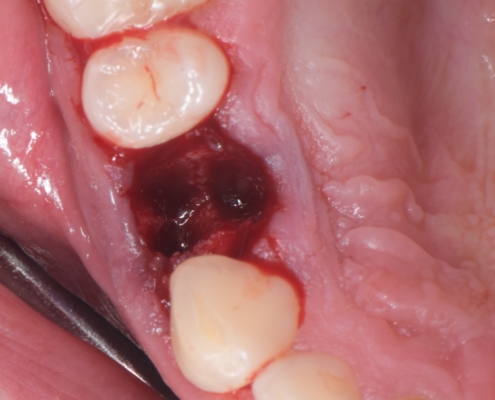

Priprema dentinskog grafta nakon ekstrakcije zuba traje 15–20 minuta., Ekstrakcijska alveola se kohleom očisti od mekih tkiva (Slika 1.). Postupak pripreme dentinskog grafta uključuje temeljito mehaničko čišćenje krune zuba od cakline, ispuna, pigmentacija, karijesa, cementa i protetskih nadomjestaka te korijena zuba od mekih tkiva (Slika 2.). Zub se potom suši pusterom i stavlja u sterilnu jednokratnu komoru uređaja Smart Dentin Grinder (KometaBio inc., Cresskill, NJ, SAD), koji ga usitnjava u čestice veličine između od 300 μm do 1200 μm (Slika 3.) te se potom odvajaju kroz sito uređaja s obzirom na veličinu u za to predviđene pretince (Slika 4.). Usitnjene čestice se zatim kemijski obrađuju otopinom natrijevog hidroksida i alkohola kroz 5 minuta, a nakon toga se dvaput ispiru fiziološkom otopinom puferiranom fosfatima, čime se postiže fiziološki pH od 7,2 (Slika 5.). Preostali vlažni dentinski graft tada je spreman za primjenu u augmentaciji (Slika 6.). Alternativno, usitnjeni dentinski prah može se sterilizirati zagrijavanjem na temperaturu od 140 °C radi potpune eliminacije bakterija, virusa i endotoksina [14]. Usitnjeni veći dijelovi zuba se postavljaju u defekt alveole (Slika 7.), radi bolje regeneracije postavlja se PRGF membrana (Slika 8.) te se završno može postaviti kolagenska spužva za potpunu adaptaciju grafta (Slika 9.). Završno slijedi postava šavova i standardna postoperativna njega.